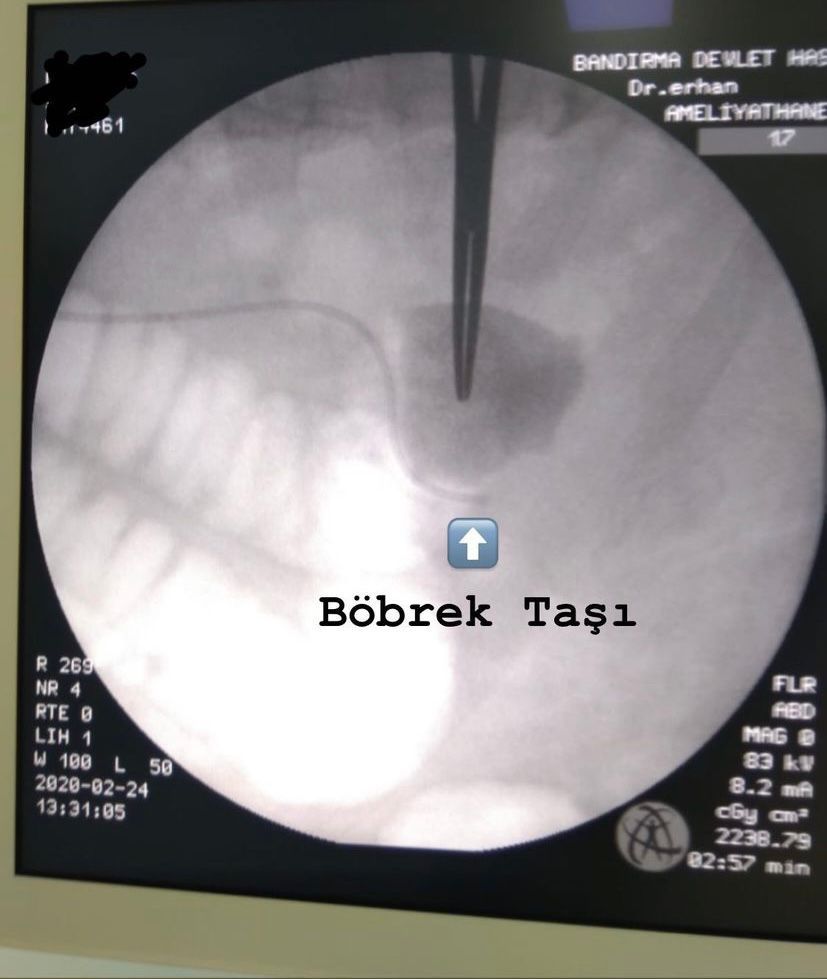

- Böbrek Taşı

Böbreğimde 47 milim taş vardı erhan bey kapalı ameliyatla taşlarımi kırıp aldı bandırmada böyle bir doktor olduğu için çok şanslıyız. Kendisi mükemmel bir doktor tavsiye ederim